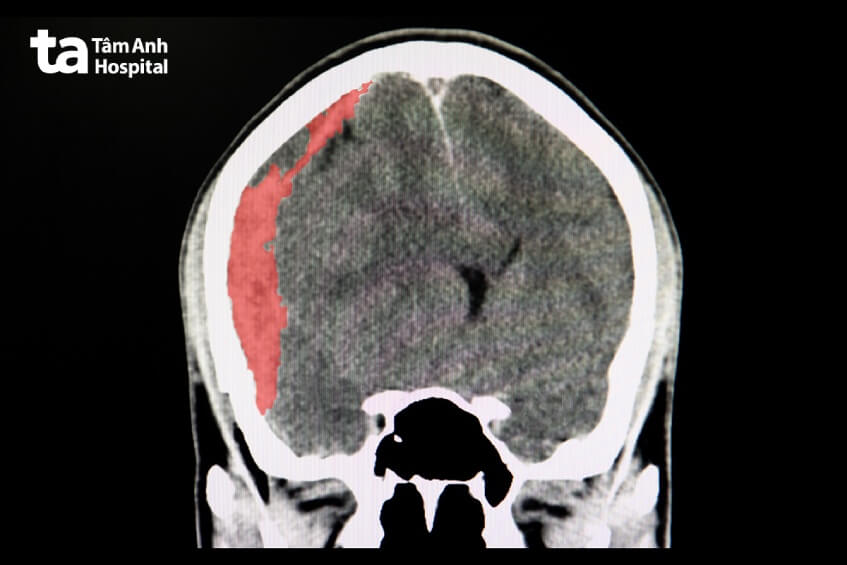

Tùy theo vị trí của khối máu tụ so với 3 lớp của màng não mà chúng có thể phân loại ra thành: tụ máu ngoài màng cứng, tụ máu dưới nhện, và tụ máu trong não,…

Khối máu tụ có thể gây ra áp lực không mong muốn lên các cấu trúc não bộ xung quanh và gây ra những triệu chứng nghiêm trọng. Các triệu chứng của tụ máu não có thể bao gồm đau đầu, mất cân bằng, mất thị giác, khó nói, và mất ý thức.

Tụ máu não cũng đòi hỏi sự chẩn đoán và điều trị nhanh chóng để giảm thiểu tổn thương não và tăng cơ hội phục hồi.

Việc phát hiện sớm và đưa người bệnh đến cơ sở y tế là rất quan trọng. Đối với các trường hợp nghi ngờ xuất huyết não hoặc tụ máu não, việc thực hiện các xét nghiệm hình ảnh như CT scan không cản quang có thể được sử dụng để xác định chính xác tình trạng và quyết định phương pháp điều trị phù hợp. Chụp quang phổ mạch máu não hoặc chụp MRI cũng có thể được sử dụng để xác định nguyên nhân và đánh giá chi tiết hơn về tụ máu khi kết quả CT scan không rõ ràng.